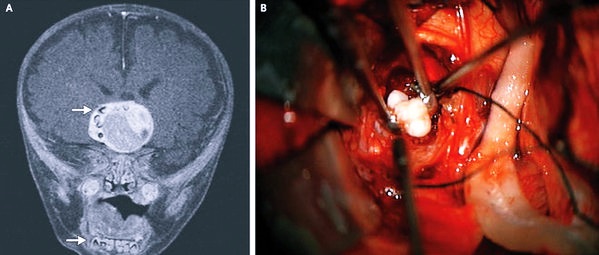

Магнитно-резонансная томография

Магнитно-резонансная томография – наиболее достоверный метод выявления мозговых опухолей. Вид новообразования на снимке представлен в форме трехмерного изображения и в тончайшем разрезе. На начальном этапе развития болезни образование на снимке выглядит в форме отека.

Диагностическому мероприятию под силу выявить даже мелкое новообразование, а также образование, место которого – возле кости или мозгового ствола.

Компьютерная томография

Компьютерная томография – менее информативный метод. С помощью КТ можно определить точное место локализации новообразования, а также сопутствующие симптомы, например, гематому и отечность.

Также проводят биопсию – забор биологического материала из новообразования, который после подвергают микроскопическому исследованию. Это позволяет определить злокачественность или доброкачественность патологии. Также исследование дает ответы о типе новообразования и его строении.